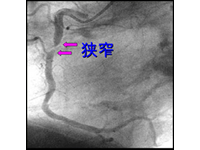

- 冠動脈が狭くなっているかどうか(冠動脈造影:図1)や、心臓の伸び縮みが正常かどうか(左心室造影:図2)分かります。

図1. 冠動脈造影検査

冠動脈の一部が狭くなっている

(矢印部)のが分かります。